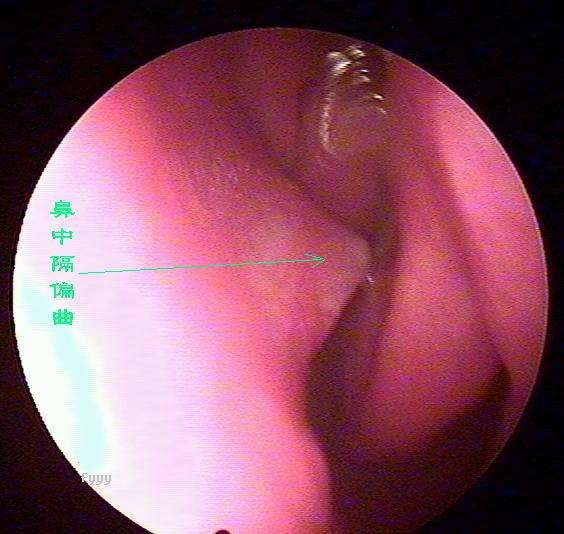

经常流鼻血是鼻中隔偏曲惹的祸

老流鼻血可能是鼻中隔偏曲惹的祸,鼻中隔偏曲部位经常会出现血管畸形,而且这里的粘膜也相对较薄,受气流、尘埃等刺激后容易破损、出血,主要症状为:交替性或持续性鼻塞,头痛,鼻出血及流脓涕等。且难以恢复,经常发作。西安新城中大耳鼻喉医院耳鼻喉科推出的立体精矫技术,快速无痛治疗鼻中隔偏曲。

鼻中隔偏曲的诊断检查

鼻中隔偏曲进行鼻内检查以判断鼻中隔偏曲的类型和程度,注意鉴别鼻中隔粘膜肥厚和是否同时存在鼻内其它疾病,如原发病变—肿瘤、异物或继发病变—鼻窦炎、息肉等。 另一罕见者为鼻中隔梅毒瘤,其质地中亦较硬,但该处粘膜明显充血。